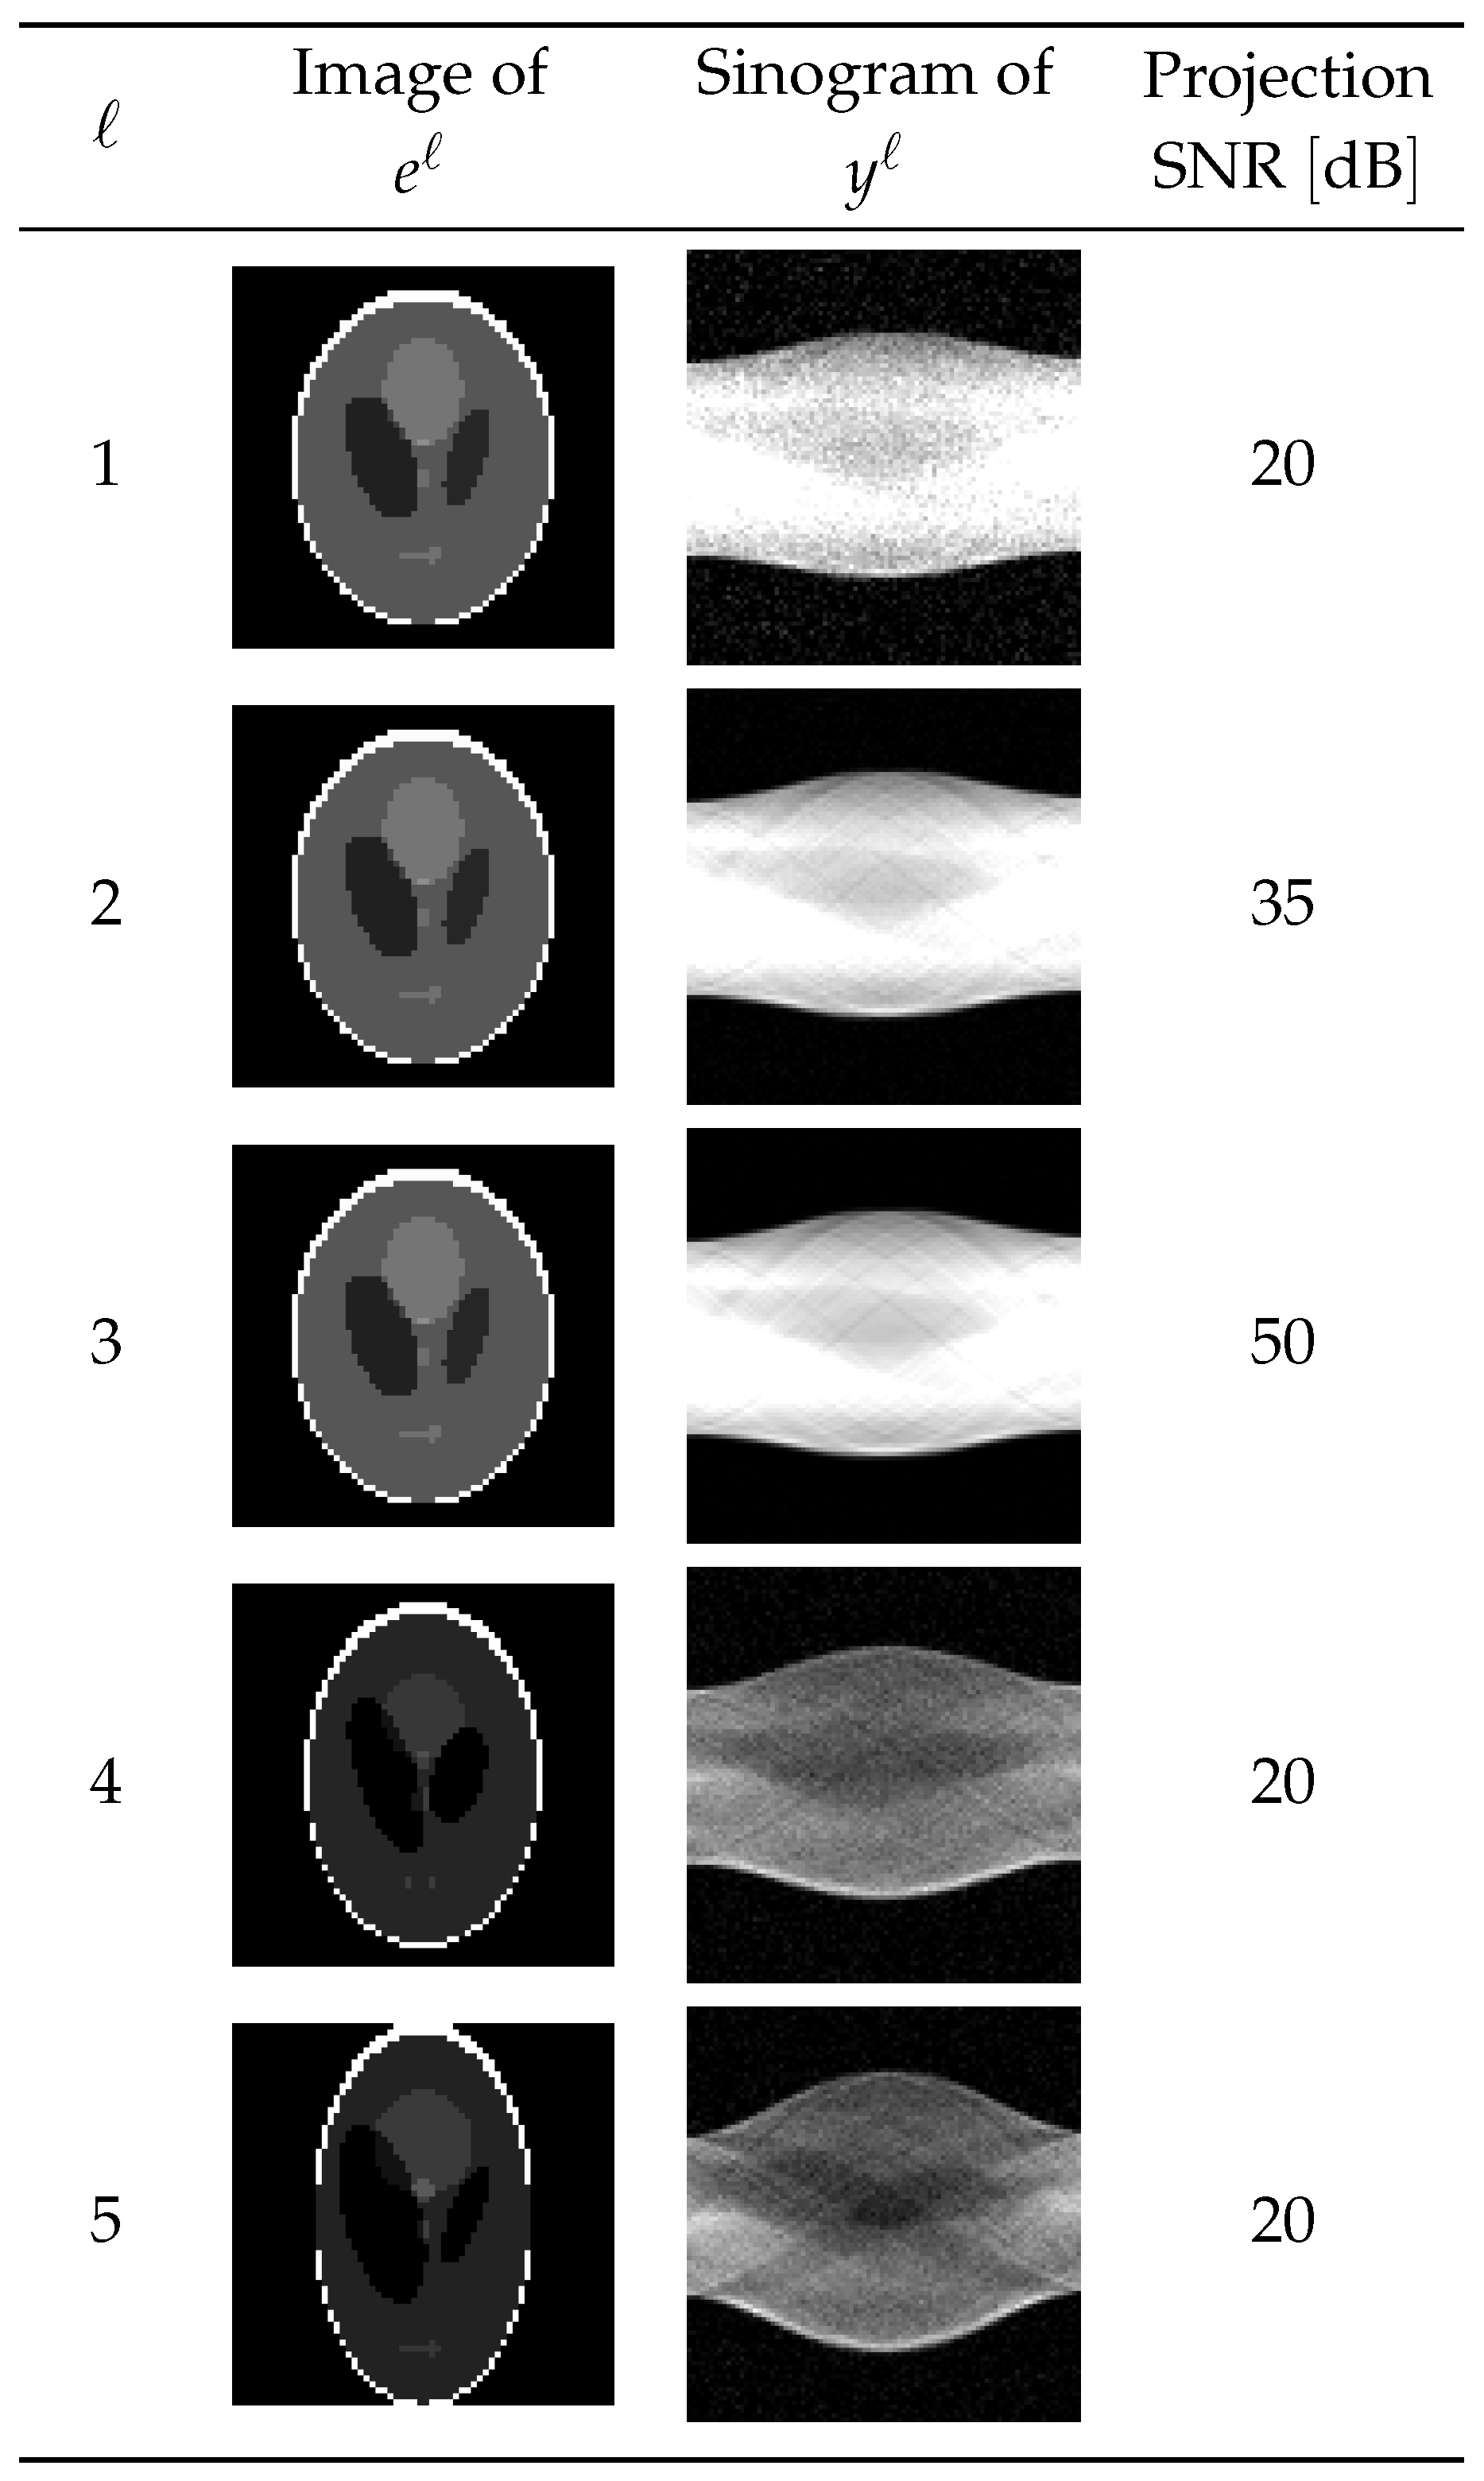

To evaluate the performance of the learned optimizer , we validated it on a test dataset consisting of data not included in the training and validation datasets. The properties described below are common to all of the test datasets. We will discuss the results for five of the test data pairs shown in Figure 9. The first test data item () was a pair of a projection with an SNR of 20 dB and the expected reconstructed image . In the second and third test data pairs ( and 3), the expected reconstructed images and equaled but with different Sn Rs of the projection. On the other hand, in the fourth and fifth test data pairs ( and 5), the expected reconstructed images and were different from and from each other, but the noise levels of the projections were 20 dB.

Figure 9.

Dataset for testing.

Figure 10 plots the evaluation function values

defined by the L2 norm of the difference between the ℓth true image and reconstructed image z when using the parameter estimated by the learned model from the projection with . The results for the MLEM algorithm, i.e., the PDEM algorithm with , are displayed for comparison.

For the first test data pair (), due to the high noise level, the evaluation functions for both the MLEM and the proposed algorithm, which is the PDEM using the parameter values estimated by the optimizer , do not decrease monotonically but rather start to increase at different iteration numbers, around and 140, respectively. The proposed method decreases the evaluation function significantly in the last iteration compared with that of the MLEM algorithm. This result indicates that the optimizer can estimate parameter values that, while not optimal, significantly improve image quality. The results for the second test data pair (), which has a different noise level than the first test data pair (), shows that the proposed method also reduces the evaluation function compared with the MLEM algorithm, but the difference is slight. We discuss the reason in the following subsection. The proposed method can significantly reduce the evaluation function when using the third test data pair (), which has weak noise. The reason for this is presumably that the power exponent parameter is a value that affects the step size in the discretization of the continuous dynamical system and that, when the noise is weak, a relatively large parameter is chosen for fast convergence to a value close to the true one. In fact, the estimated parameter is 1.64, which is larger than the others. The results for the fourth and fifth test data pairs ( and 5), where the projection contains a lot of noise, show a slight decrease in the value of the evaluation function, contrary to the results for the first test data pair (), where the SNRs of the projections are comparable. This result suggests that the optimal parameters also depend on the shape of the reconstruction target.

Figure 11 shows the contour maps of the evaluation function values of the reconstructed image for changes in the parameters and according to the projection . On all the test data, the optimizer could estimate parameters that reduce the evaluation function value more than the MLEM algorithm. In the case of and , where significant improvements were observed, the region of suitable parameters is located far from corresponding to the parameter for MLEM, and the optimizer succeeds in estimating the values around it. On the other hand, for , and 5, where the differences in the evaluation functions are slight, the optimal parameters are relatively close to . In other words, these cases are problem settings in which the MLEM algorithm can achieve high performance. Even in such cases, our optimizer can estimate the parameters better than it can. The previous study suggested the possibility of a rough parameter estimation by using the noise level. Indeed, the results for , and 5 show similar trends in the contour plots for the same noise level, and the results for and 3 show a significant change in trend with the noise level. However, the optimal parameter values and contour maps depend not only on the noise level but also on the shape of the reconstruction target.